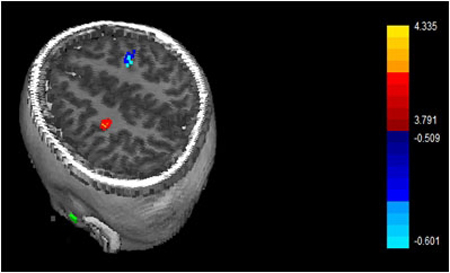

- Differentiate between the brain oscillation properties, based on magnetoencephalography (MEG), regulating the development of sensorimotor substrates in children with diplegic cerebral palsy

- Differentiate between the brain oscillation properties and neural connectivity patterns regulating the development of sensorimotor processing substrates in children with hemiplegic cerebral palsy